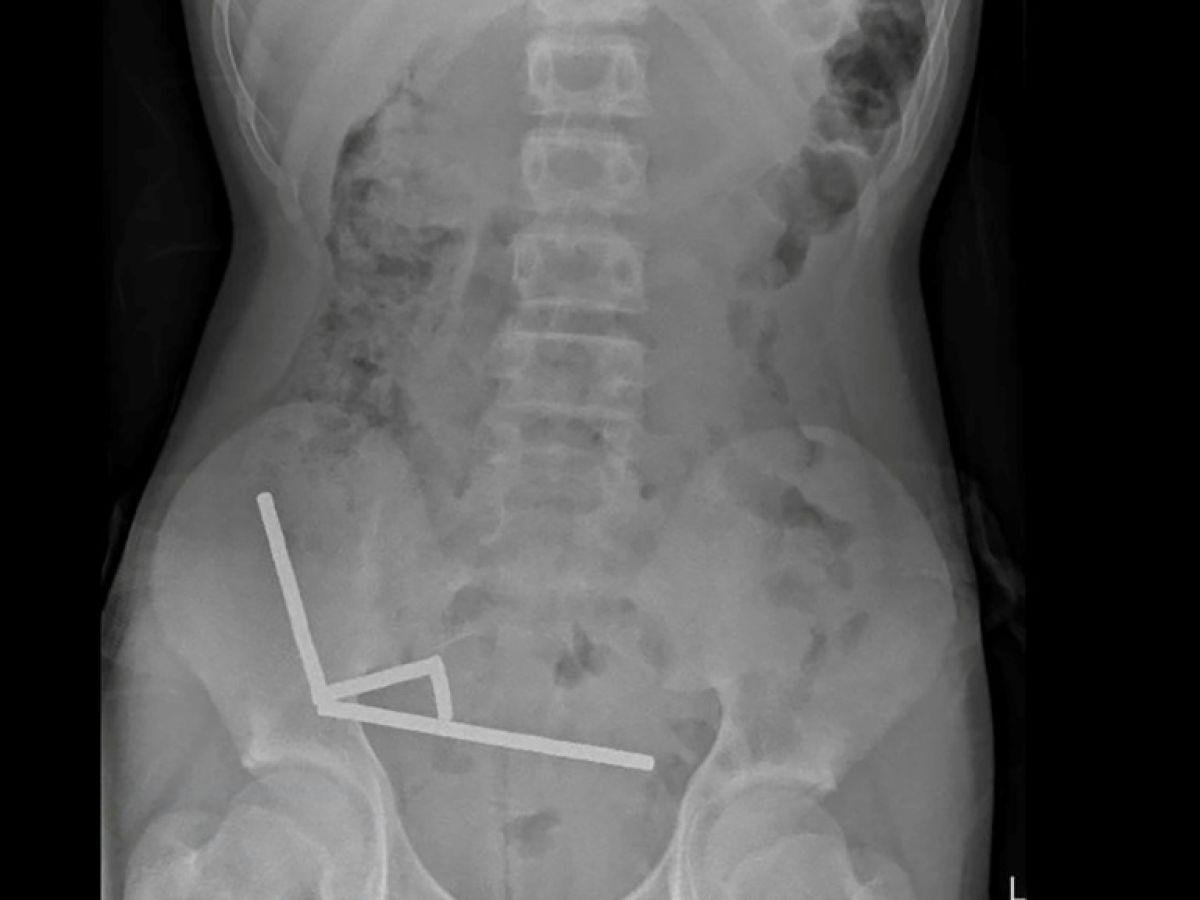

« Il avoué avoir ingéré entre 80 et 100 aimants puissants au néodyme, de 5x2mm environ, une semaine plus tôt », indique un rapport des médecins de l’hôpital de cet hôpital, publié dans le New Zealand Medical Journal (NZMJ).[Lire l'article en intégralité]